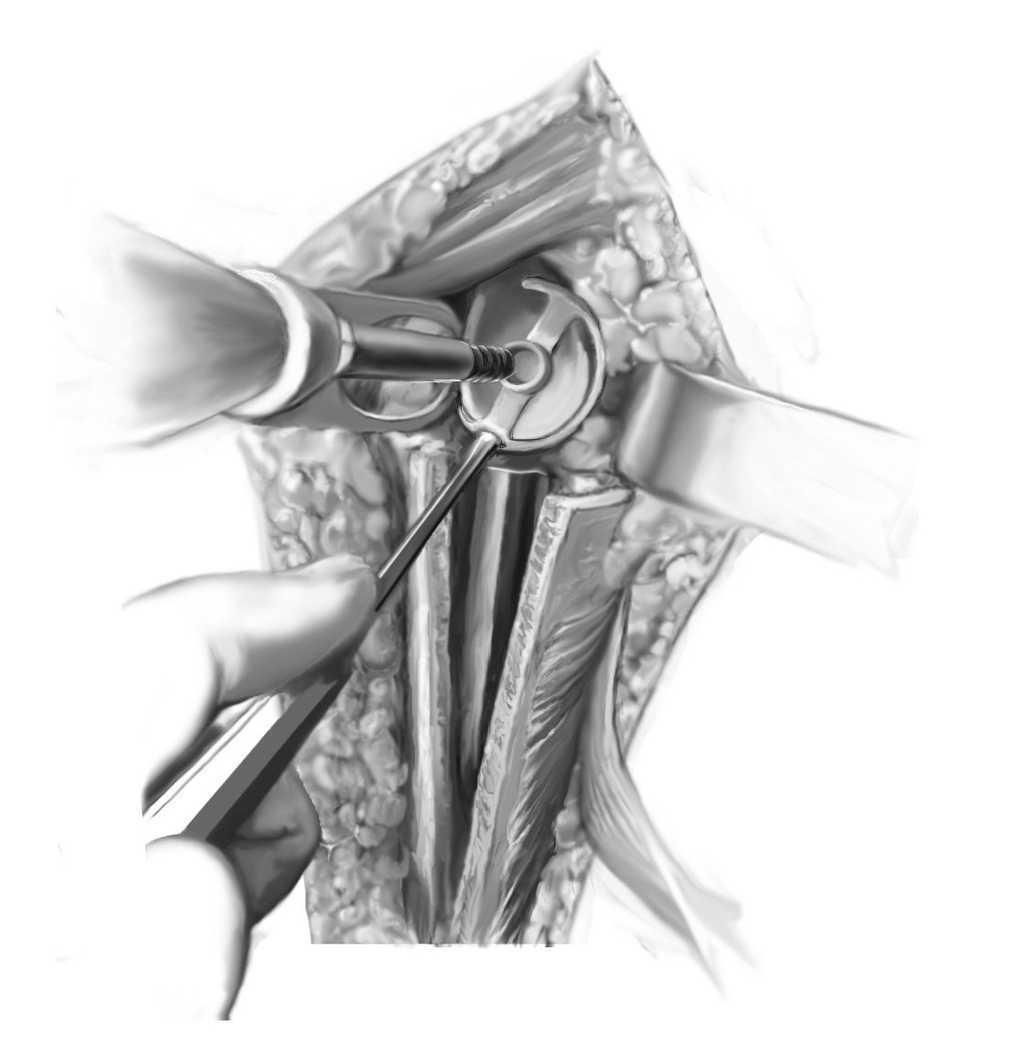

Figura 7. Fijación de la metaglena colocada. Tras colocar la metaglena, se introduce la glenosfera y se fija con el tornillo central de bloqueo. Se vuelve a exponer la diáfisis humeral y se introduce el implante de prueba del tamaño adecuado. Esto debe recuperar la longitud humeral apropiada. Una vez realizada la reducción de prueba, deberÃa ser necesario aplicar una tracción moderada sobre el húmero para poder luxar. Se puede utilizar una referencia aproximada, con el brazo en abducción de 40º se aplica tracción en dirección axial: no debe observarse una distracción mayor a la anchura del dedo meñique. Básicamente, son ciertas las siguientes afirmaciones: cuanto mayor sea el defecto de partes blandas y la pérdida de hueso metafisario, más tensas deben quedar las partes blandas. Si se ha logrado una posición estable, se pueden marcar en la prótesis la retroversión adecuada y el nivel de anclaje con un rotulador, posiblemente la distancia entre la parte más alta del último vástago colocado y el hueso residual. Se coloca un tapón intramedular reabsorbible dentro del húmero distal a la altura predeterminada. Se ensambla el implante humeral para corresponder a la longitud del implante de prueba y se introduce en el húmero distal.

Figura 8 Nueva introducción del componente humeral después de cementar, y colocación del polietileno. Antes de la colocación definitiva, se prepara el cerclaje alámbrico dejándolo listo para estabilizar la ventana ósea. El recubrimiento del componente humeral con cemento óseo es útil para obtener una distribución uniforme del cemento en lo que habitualmente es una cavidad medular muy estrecha. Los implantes de revisión sin bloqueo de la modularidad (de DePuy) se pueden bloquear modelando el cemento en la parte proximal del componente humeral. Colocación del implante humeral con la altura y retroversión previstas. No se cierra la ventana ósea hasta que el cemento de la cavidad medular distal se ha endurecido. Después de valorar de nuevo la estabilidad articular con los componentes de prueba y después de colocar el polietileno definitivo de la altura requerida (3-12 mm, dependiendo de la casa comercial), se recoloca la ventana ósea utilizando los cerclajes previamente preparados y/o pinzas de reducción. La fijación de la ventana ósea se puede reforzar mediante un segundo recubrimiento de cemento en el vástago proximal.